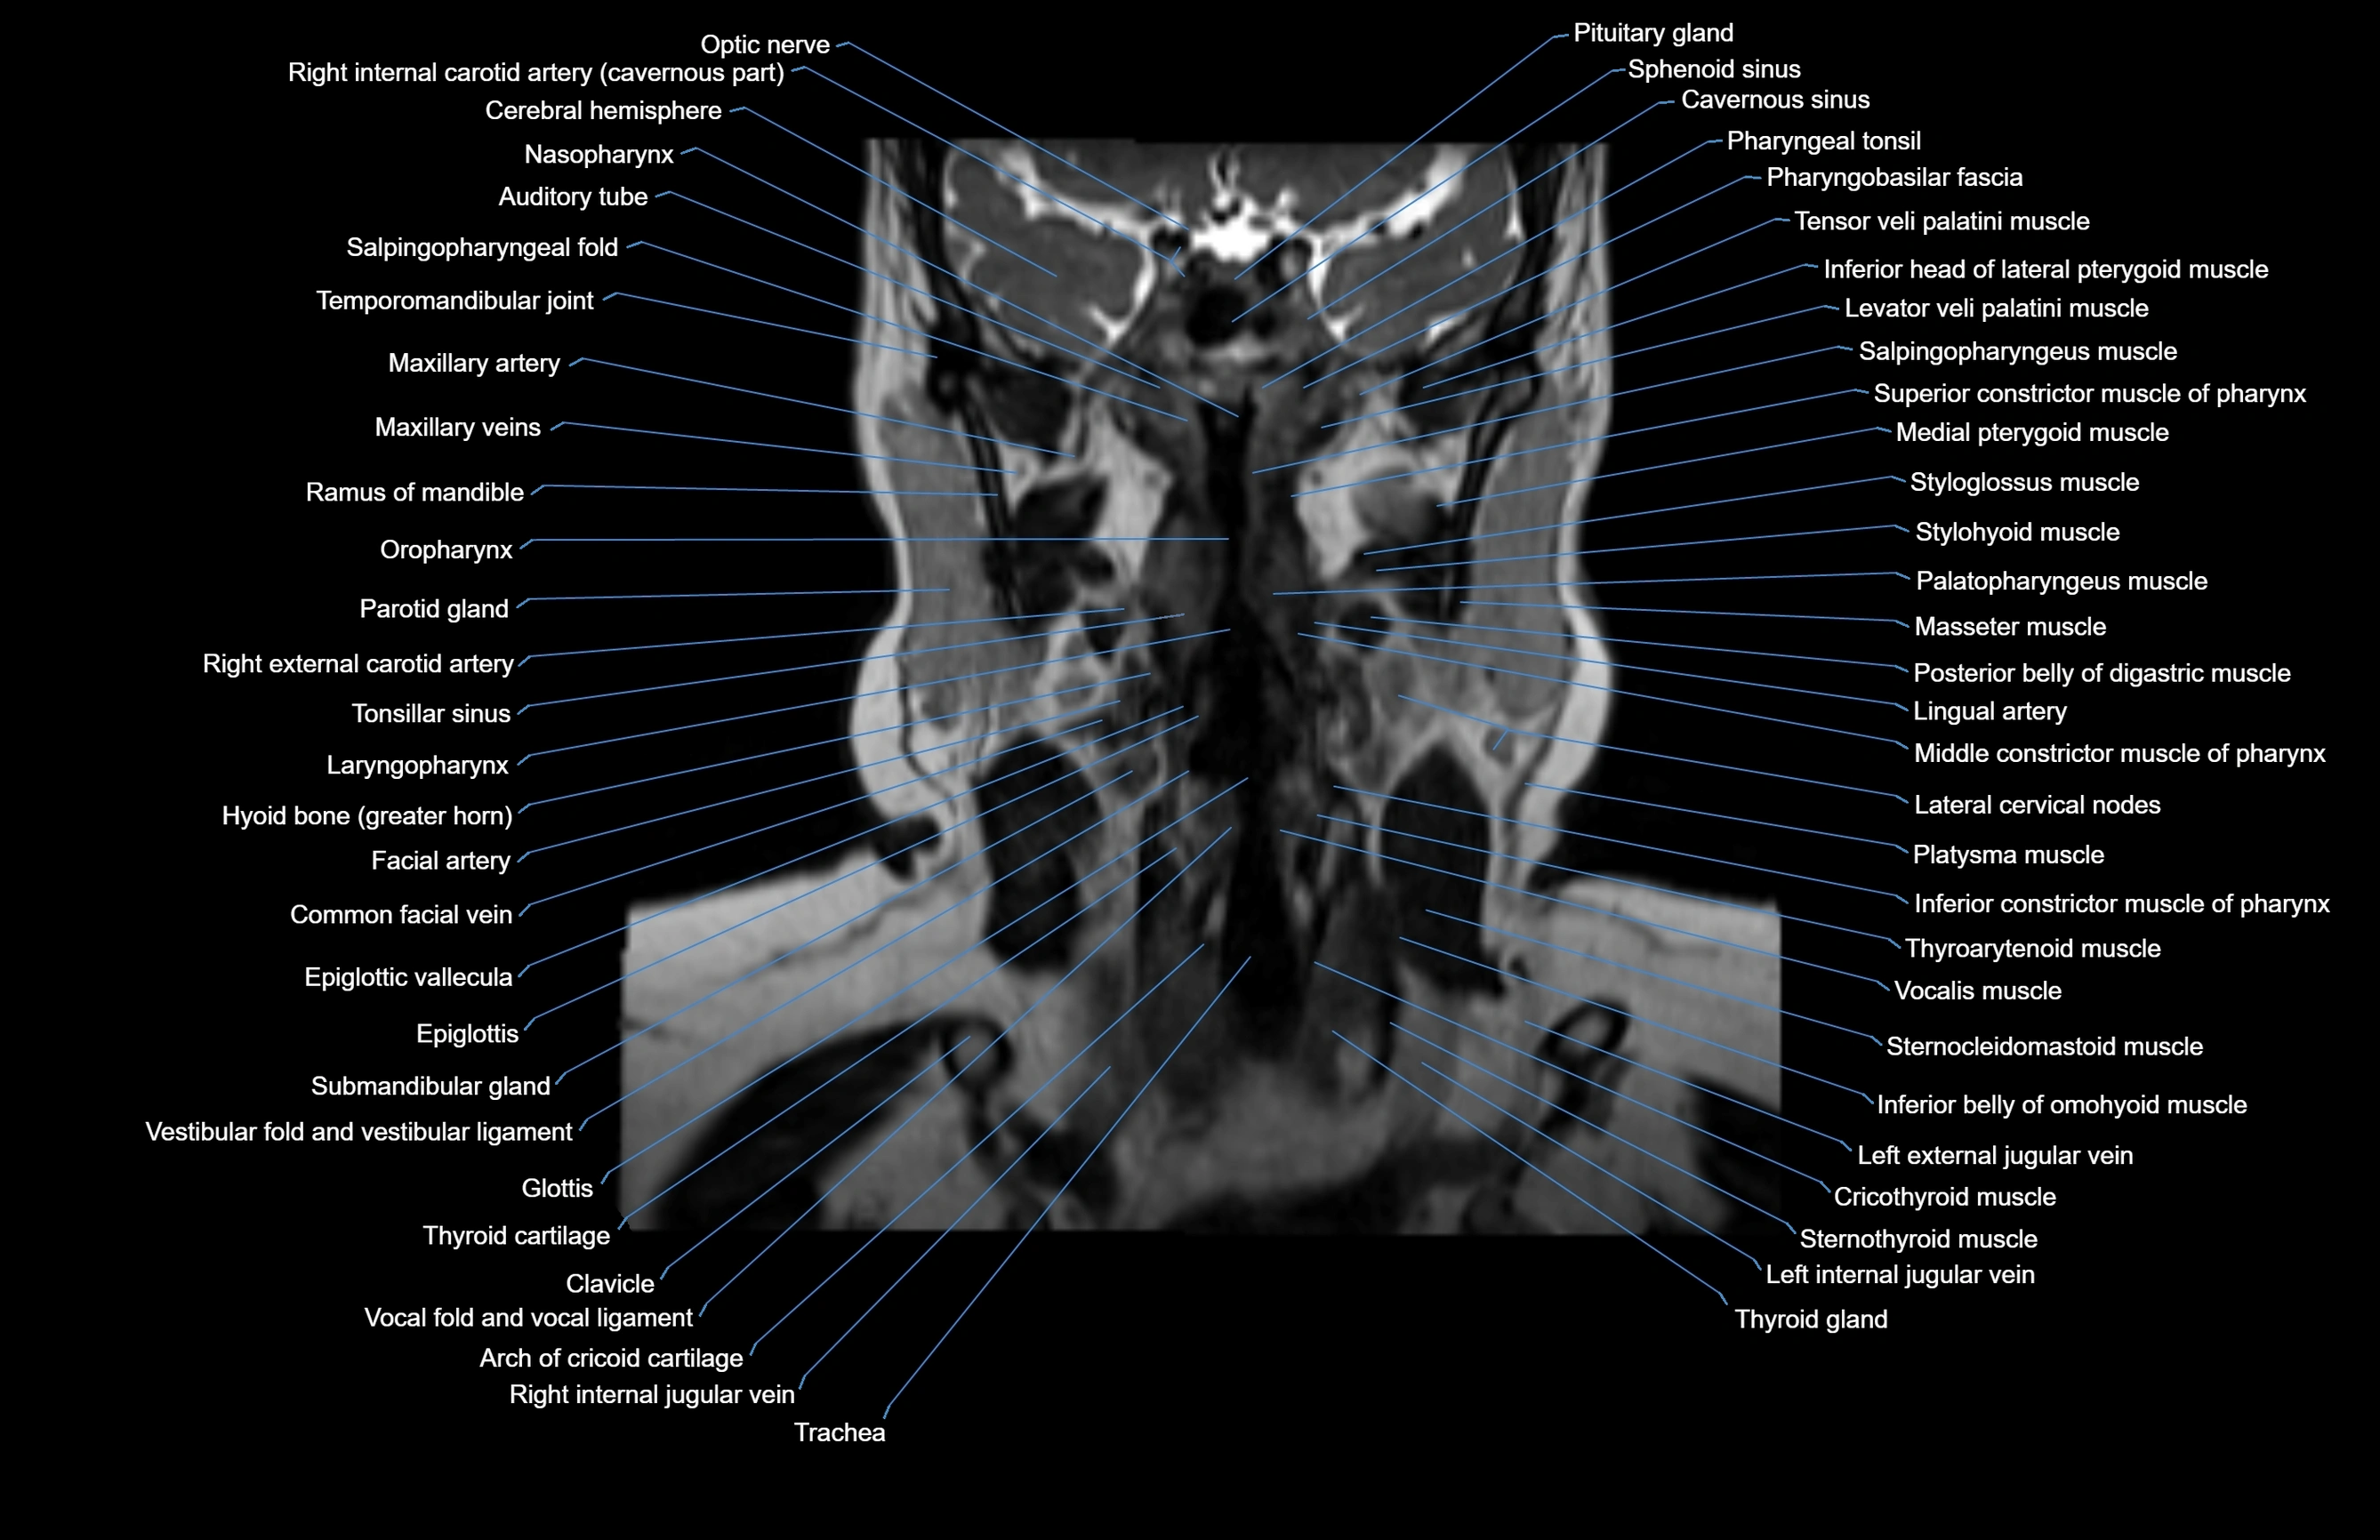

MRI images